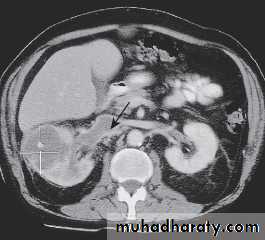

Renal adenocarcinoma. A In this CT, the right kidney is expanded by a low-density tumour, which fails to take up contrast material. Tumour is shown extending into the renal vein and inferior vena cava (arrow). B Pathology specimen showing typical necrosis.

B

A